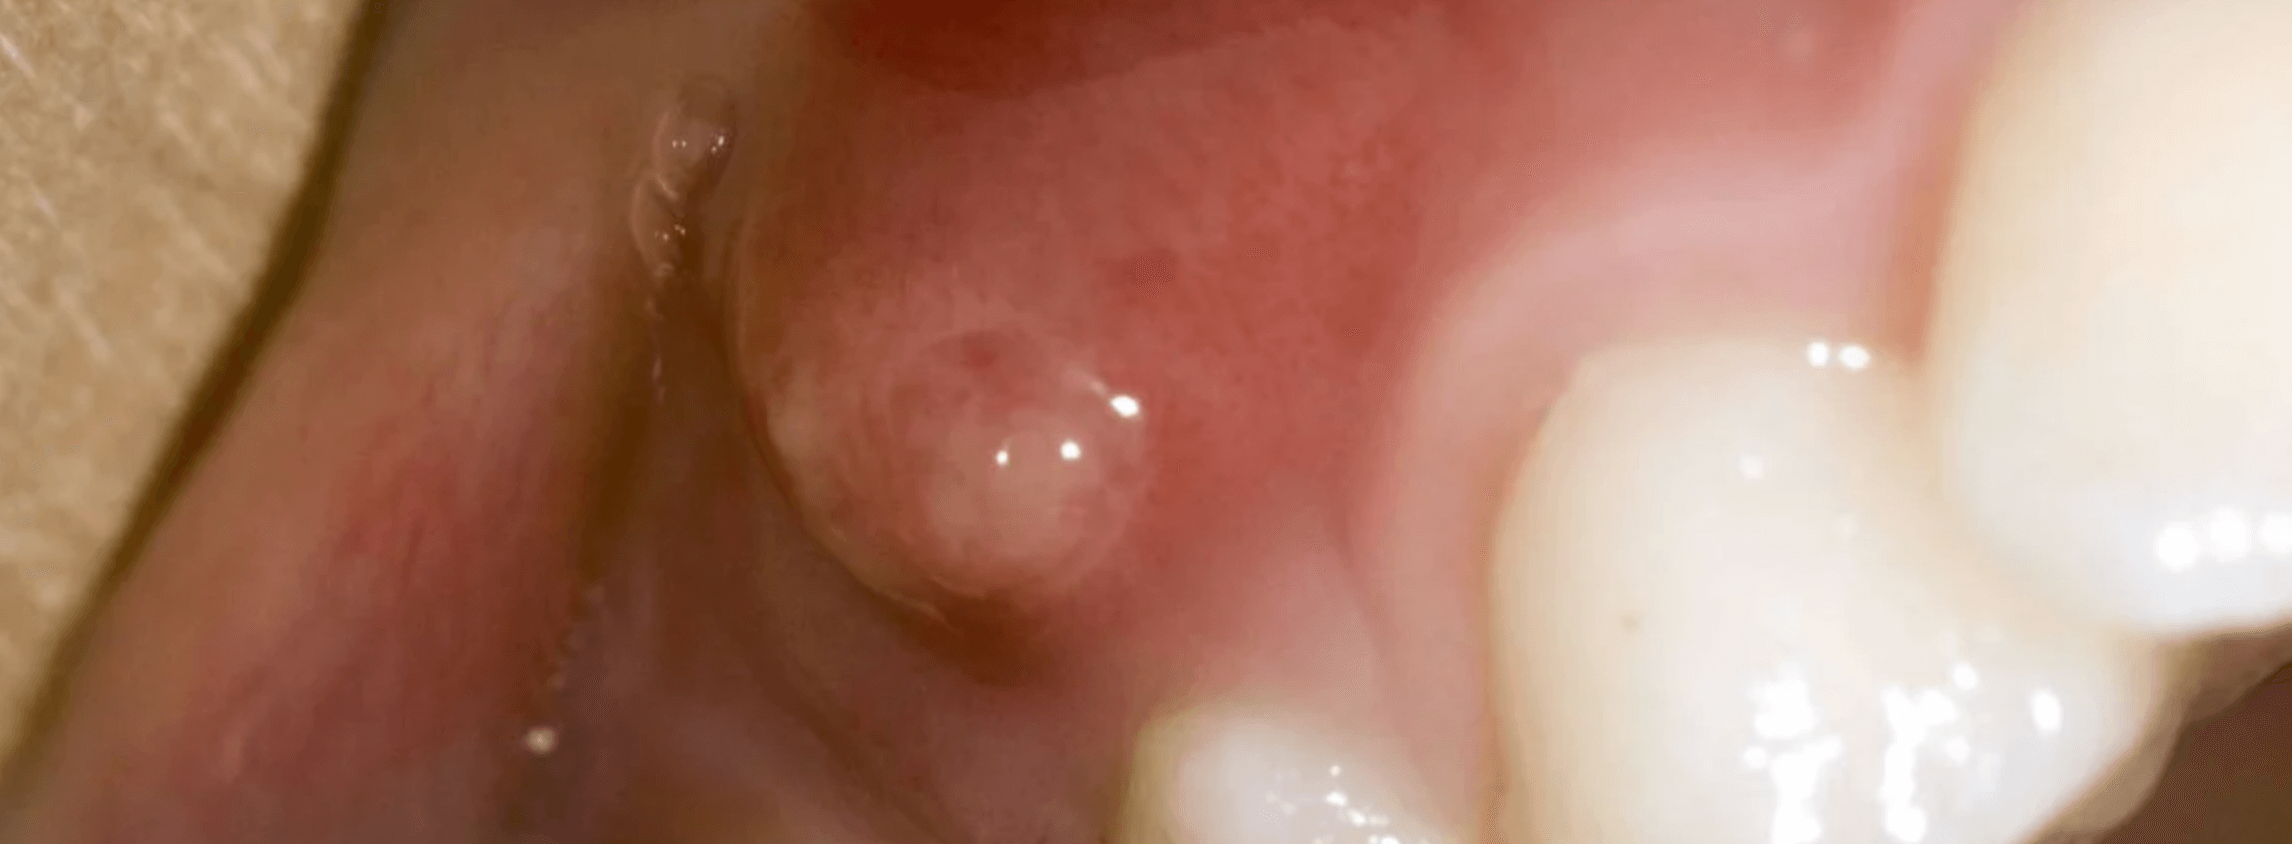

잇몸에 고름주머니가 생기면 최대한 빠르게 치과에 와서 치료를 받는것이 좋습니다. 잇몸 고름주머니는 염증이 생겨 고름이 빠져나가지 못하는 고름이 뼈를 녹여 잇몸이 부풀어 오른경우를 말합니다. 이러한 잇몸 염증 치주 농양 치료법과 비용에 대한 정보를 공유 합니다.

일반적으로 잇몸에 고름이 생기는것을 치주 농양이라고 이야기를 합니다. 이러한 잇몸 고름주머니는 심각한 잇몸 질환 치주염으로 인해 발생할수 있으며, 이로인해 박테리아가 자랄수 있는 고름주머니가 생길수 있습니다.

또한 치석이 너무 많이 쌓이거나 음식물이 주머니에 끼면 고름이 발생하게 되고 이러한 고름이 배출되지 않으면 치주 농양이 형성되게 됩니다. 치주 농양은 인근 치아에 발열과 같은 통증을 유발하고 치아와 잇몸의 뼈를 녹이거나 잇몸을 손상시켜 치아가 흔들리고 빠질수 있습니다.